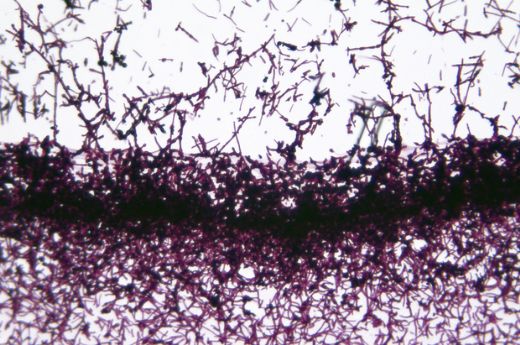

Tanı, genellikle dermatolog tarafından cilt muayenesi ile konulmaktadır. Gerekirse, cilt örneği alınıp mikroskop altında incelenebilir. Tedavi Yöntemleri Cilt mantarlarının tedavisi, enfeksiyonun türüne ve şiddetine bağlıdır. Tedavi yöntemleri şunlardır: